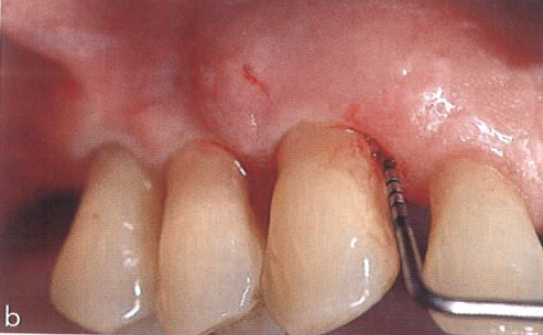

在之后的每次随访复诊中,该区域都被密切监测,并且在使用半导体激光治疗后1年,临床状态似乎已经稳定。图3为急性发作5年后的牙周情况,总随访时间为20年。这张图片说明患者的牙周状况保持稳定,探诊深度约为3 mm,无探诊出血。

图3  急性发作5年后,患者探诊深度约为3 mm,无探诊出血,牙周状况保持稳定